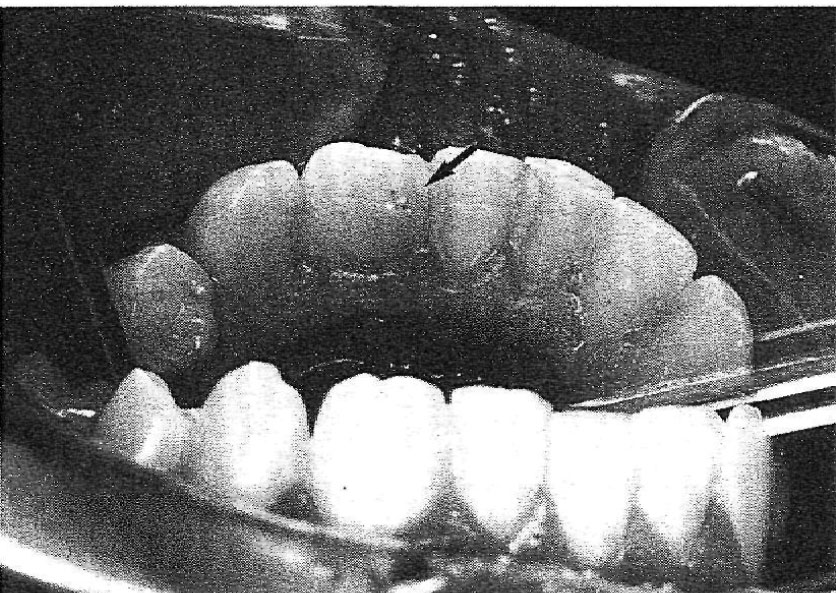

A 25-year-old Greek male complaining of acute pain in the right mandibular lateral incisor (42) was referred to the Endodontic Clinic at the University of Athens. The patient's medical and dental history was uncomplicated. The clinical examination showed that the tooth was tender to percussion and palpation, but free of decay, Pulp sensitivity tests (thermal and electrical) were negative. There was no history of trauma and the patient had no harmful habits. The crown of tooth 42 was wider than that of the left mandibular lateral incisor (32). In the labial surface of the crown, there was a groove, and in the lingual, a pit. The colour of the tooth did not differ from the adjacent teeth and the total number of teeth in the arch was normal (Figs 1 & 2). Radiographic examination revealed that the tooth had a single broad root with two separate root canals. ln the mescal pulp cavity, there was a dens invaginatus extending through the root and opening in the apical region. In the periapical region, there was a radiolucency (Fig. 3).